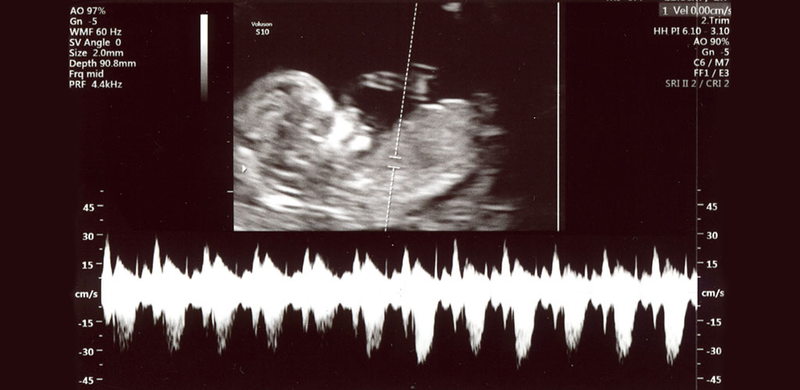

W Holandii rodzi się rocznie około 600 dzieci z rozszczepionym kręgosłupem i innymi ciężkimi deformacjami czyniącymi je niezdolnymi do życia. Zdarza się to w każdym szpitalu kilka razy w roku. Co miał robić lekarz któremu nie wolno aktywnie zakończyć życia takiego dziecka? W roku 2005 powstał protokół z Groningen  który miał takim dylematom zapobiec. Od 2005 roku wykonuje się echoskopię (USG) kobiet w 20 tygodniu ciąży aby wcześnie wykryć wszystkie nieprawidłowości i ewentualnie wykonać aborcję. Ta regulacja miała problem rozwiązać. Niestety pozostał jeszcze niewielki procent noworodków, szczególnie tych z uszkodzonym mózgiem (także drastyczne wypadki uszkodzenia mózgu przez niedotlenienie podczas porodu) które przychodzą na świat choć nie są zdatne do samodzielnego życia; mogą nie mieć funkcji ssania, oddychania, nie widzą i nie słyszą. Podtrzymywane są przy życiu przez aparaturę i kroplówki. Aktywnie zakończyć ich życia nie można ("aktywnie" czyli przez podanie usypiających środków farmakologicznych) jakie są więc alternatywy? W takich beznadziejnych wypadkach rodzice sami proszą lekarzy o zakończenie życia dziecka. Ponieważ aktywne zakończenie jest karalne - lekarzowi pozostaje odłączenie aparatury i czekanie na śmierć naturalną. Czasami natura jest silniejsza niż nam się zdaje. Taki noworodek potrafi żyć jeszcze kilka tygodni. Umiera w oddzielnym pokoju z głodu i pragnienia. Rodzice patrzą na to codziennie. Wyschnięty, pomarszczony noworodek umiera. Eutanazji nie było.